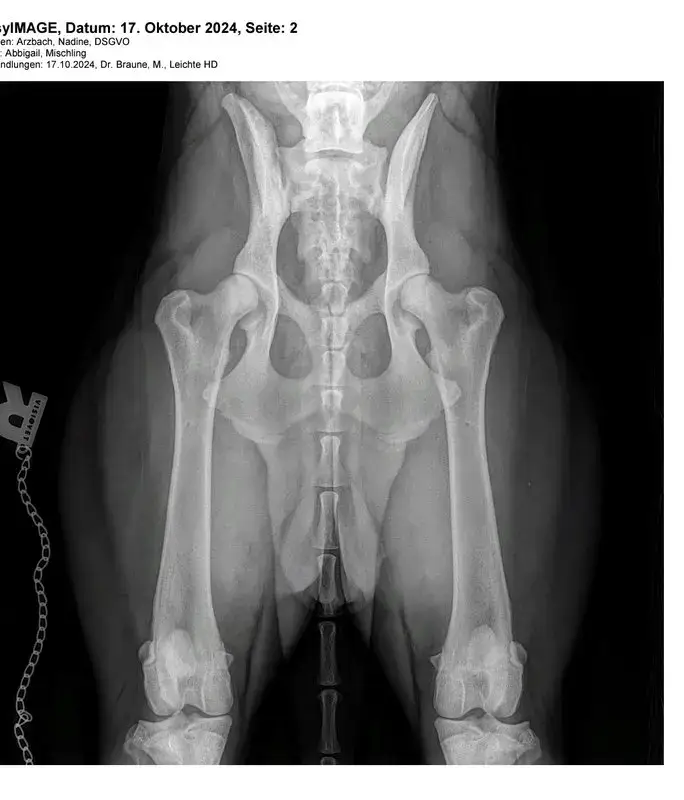

Bin dann gespannt, was die Kenner antworten. Links ist die Überdachung weniger als rechts, aber wie eine Tophüfte im Vergleich aussieht würde mich auch interessieren.

Die hd soll rechts sein , ja ganz schlecht finde ich die nichz. Aber man sieht bei dem einen bild zb das die wirbelsäule minimal schief geht. Somit dschte ich als laie nicht exakt gelagert

Für mich als Laie sieht es nicht perfekt aus, aber auch nicht ganz übel.